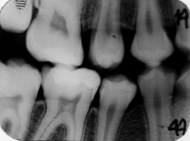

Radiografiile bitewing sunt insa esentiale pentru diagnosticul leziunilor aproximale daca sunt realizate corect, in conditiile in care punctele de contact nu se suprapun si nu exista inghesuire posterioara.

Leziunea posterioara apare ca o arie triunghiulara intunecata in smalt. Se poate afla pe suprafata externa a smaltului sau in profunzimea acestuia.